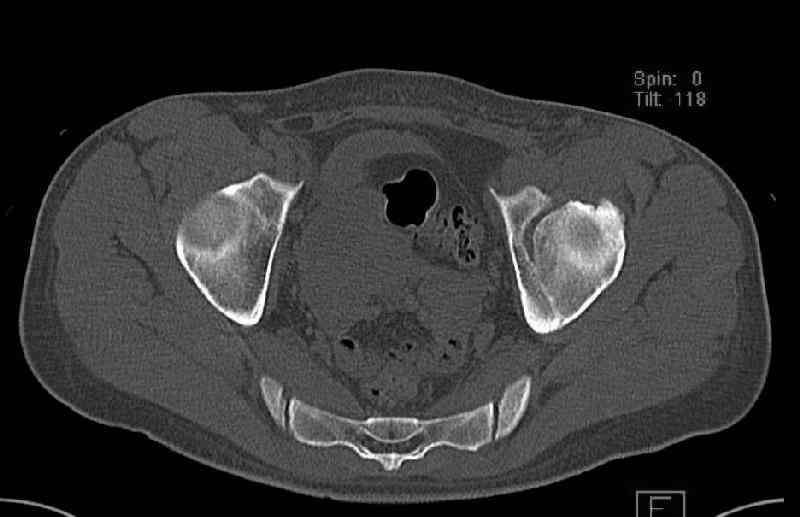

The last two images from the 3-D CT scan certainly makes the fracture look worse than the plan radiographs.

The joint is non-concentric as the head appears to be either "following the caudal segment", or the dome component is displaced from the tethered head... or so it seems... and he's young... so, many fracture surgeons would recommend reduction and fixation.

So we must decide preoperatively which part is the displaced segment?

It's difficult to know from these few selected images which component of the injury (was before and now) should be deemed the "soon to be mobile"

segment. It's my best guess that it is the caudal portion and there exists a healing fracture line somewhere thru the posterior column...one image

suggests it. If true, its early healing/union should be disrupted, and the resultant fragment mobility then allows accurate reduction.

On the other hand, some surgeons advocate an extended iliofemoral exposure for these scenarios. For a variety of reasons, I've never been much of a fan.

In summary, reduction and fixation would be good. If you have an excellent 3D brain, a quality OR fluoroscopy unit, and are slick with an osteotome and clamps thru the ilioinguinal exposure then you've made your best choice.

Some more images. Does it help to guess which part of the acetabulum is displaced?

Normal appearing SI joints and a healed posterior column limb... my bet's on caudal segment displacement.